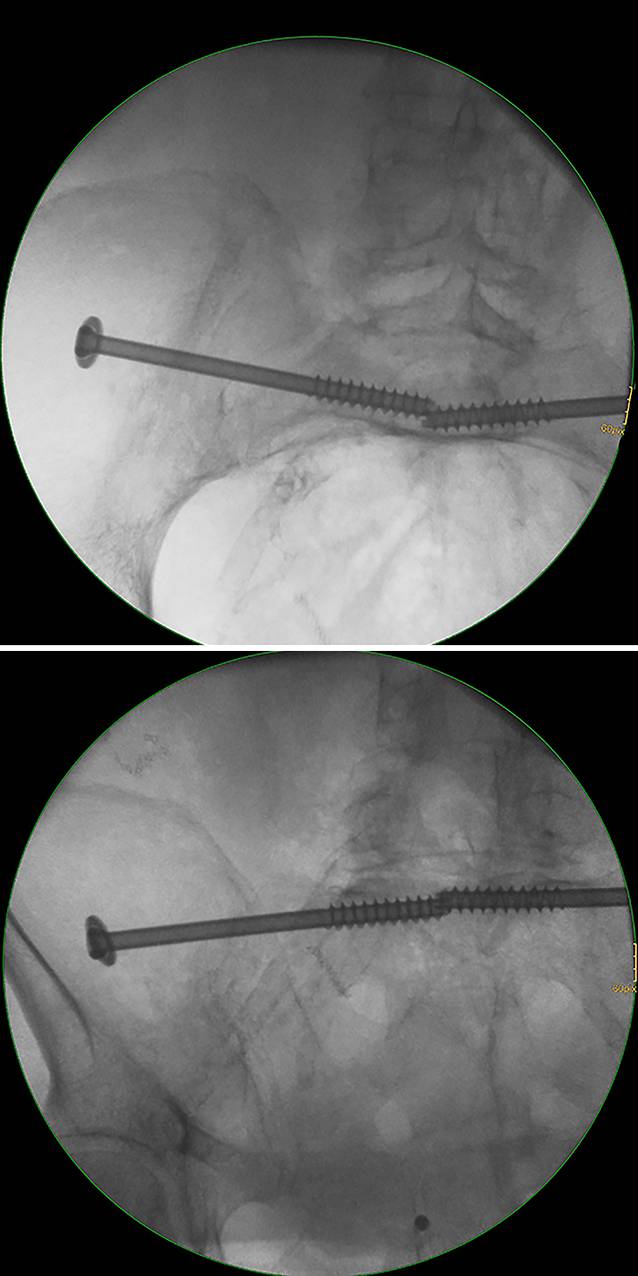

Fig. 7

Advancing the guide wire, predrilling and screw implantation. a The guide wire is advanced across the sagittal midline in transforaminal sacral fractures. In SI joint disruptions the guidewire should be advanced at least to the extent that the thread (16 or 32 mm) is completely medial of the SI joint in order to obtain a lag screw effect. b Predrilling is performed across the SI joint for a total of three cortices. c A cannulated 6.5 mm fully threaded cancellous screw is inserted over the guide wire as a position screw without compression of the transforaminal sacral fracture

Bild vergrößern